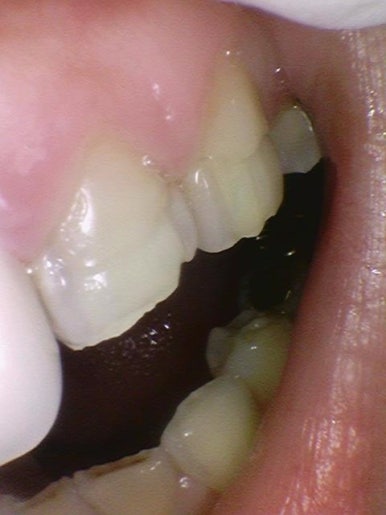

치료 전 처음 내원시 사진

환자분은 치아들이 부식되어 노랗게 보이고 약해져있다며

라미네이트 상담을 하기위해 오신 분이었습니다.

앞니3개에는 오래 전에 한 크라운이 되어있는 상태였는데

모양과 색이 맘에 들지 않는 상태였습니다.

뿐만 아니라 치아들이 단단한 겉면인 건강한 상태가 아니라

단단하지 않고 상아질이 많이 보이는 부식된 상태였습니다.

이의 표면이 녹은 상태 등으로 볼 수 있고,

섭식장애나 구토 등이 있는 사람들에게서 보기 쉽습니다.

정상적이거나 일반적이지는 않은 치아 상태입니다.

자연적으로 부식되어 있는 치아